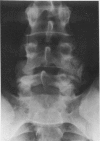

We present four cases of massive unilateral lumbar facet joint hypertrophy in an otherwise morphologically normal spine. All presented with a combination of low back pain and symptoms of entrapment of a single lumbar nerve root. The abnormality is best visualised by CT scanning and the results of surgical decompression by partial undercutting facetectomy are favourable.